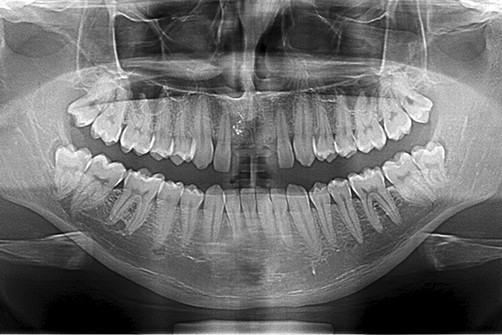

Umożliwia on wykonanie zdjęć panoramicznych – OPG, które uwzględniają obraz całości kości szczęk i żuchwy, całego uzębienia oraz pozostałych szczegółów anatomicznych takich jak zatoki szczękowe, nos, stawy skroniowo żuchwowe oraz oczodoły

Obraz diagnostyczny przedstawiany jest w dwóch wymiarach co ogranicza przestrzenną analizę interesującego nasz obszaru anatomii pacjenta. Zdjęcie panoramiczna w połączeniu z klinicznym badaniem jamy ustnej pacjenta daje pełną, podstawową informację odnośnie diagnozowanego obszaru.

Zdjęcie pantomograficzne, zwane również panoramicznym, to specjalistyczne badanie obrazowe używane do celów stomatologicznych. Wykonujemy je, gdy istnieje potrzeba zobrazowania wszystkich zębów szczęki i żuchwy (również tych zatrzymanych), zatok szczękowych, stawów skroniowo-żuchwowych, a także otaczających tkanek.

Wykonujemy je, ustawiając pacjenta przed kolumną aparatu, następnie polecamy, aby zagryzł specjalny ustnik, przez co uzyskujemy właściwą pozycję głowy, która gwarantuje odpowiednią projekcję. Podczas badania należy przez kilka sekund zachować bezruch oraz wykonywać polecenia technika. W trakcie badania głowica pantomografu krąży wokół głowy pacjenta przez kilka sekund, a uzyskany obraz jest od razu widoczny na monitorze.